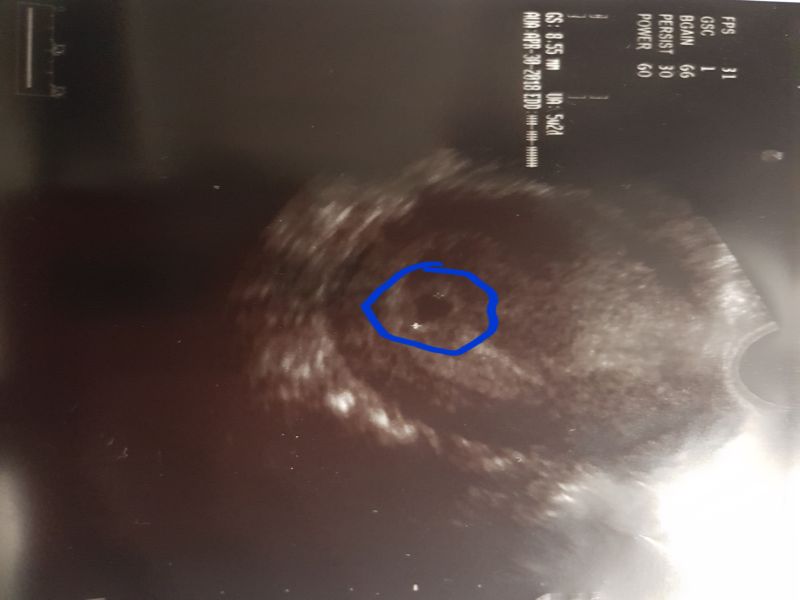

Ja mam takie zdjęcia i kompletnie nie wiem co na nich mam widzieć

To okrągłe to chyba pęcherzyk ?